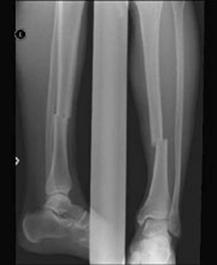

Fracturi simple: SPIRALA OBLICA TRANSVERSALA

Fractura spirala de Fractura transversa de diafiza femurala Fractura spirala de diafiza tibiala

diafiza humerala

Fractura spirala de diafiza tibiala Fractura oblica de diafiza tibiala Fractura transversala de diafiza tibiala

Fracturi cominutive

Fracturi spirala cominutive de Fractura complexa de diafiza radiala diafiza humerala